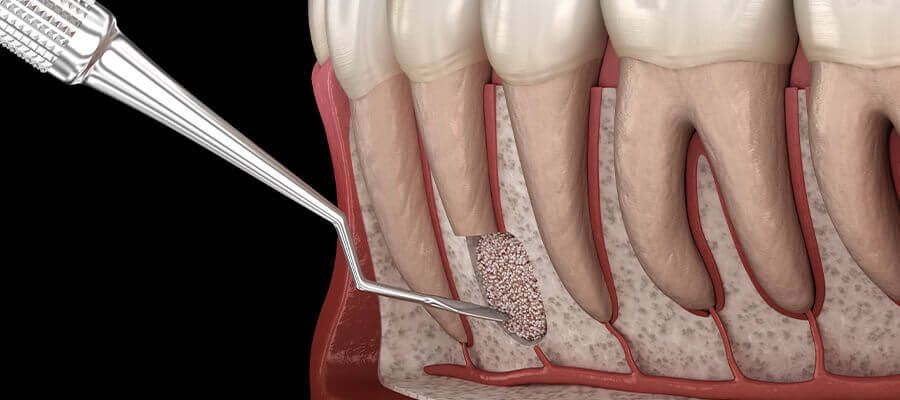

Rekonstrukcja i regeneracja tkanek za pomocą biomateriałów

Po utracie zęba, czy to w wyniku urazu, czy choroby, nierzadko konieczna jest odbudowa kości lub dziąsła. Korzystamy z najnowszych technologii, aby przywrócić Pacjentom pełną funkcjonalność i estetykę jamy ustnej.